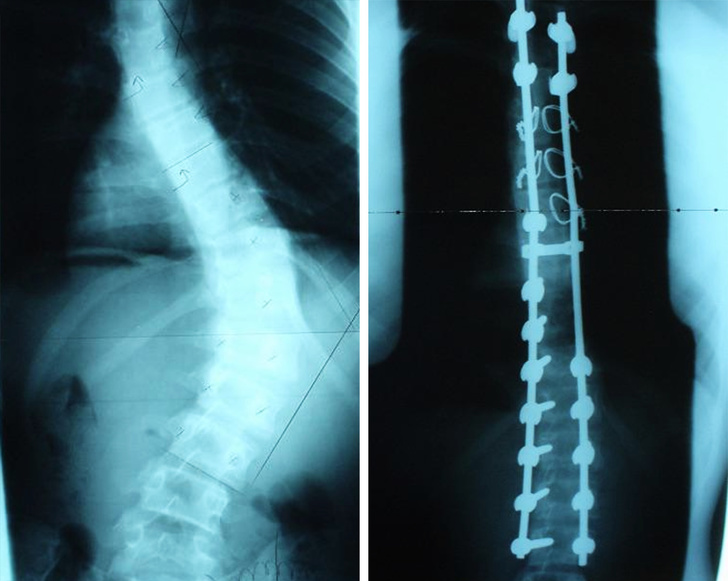

6. Ακτινογραφία ασθενή με σκολίωση, πριν και μετά το χειρουργείο